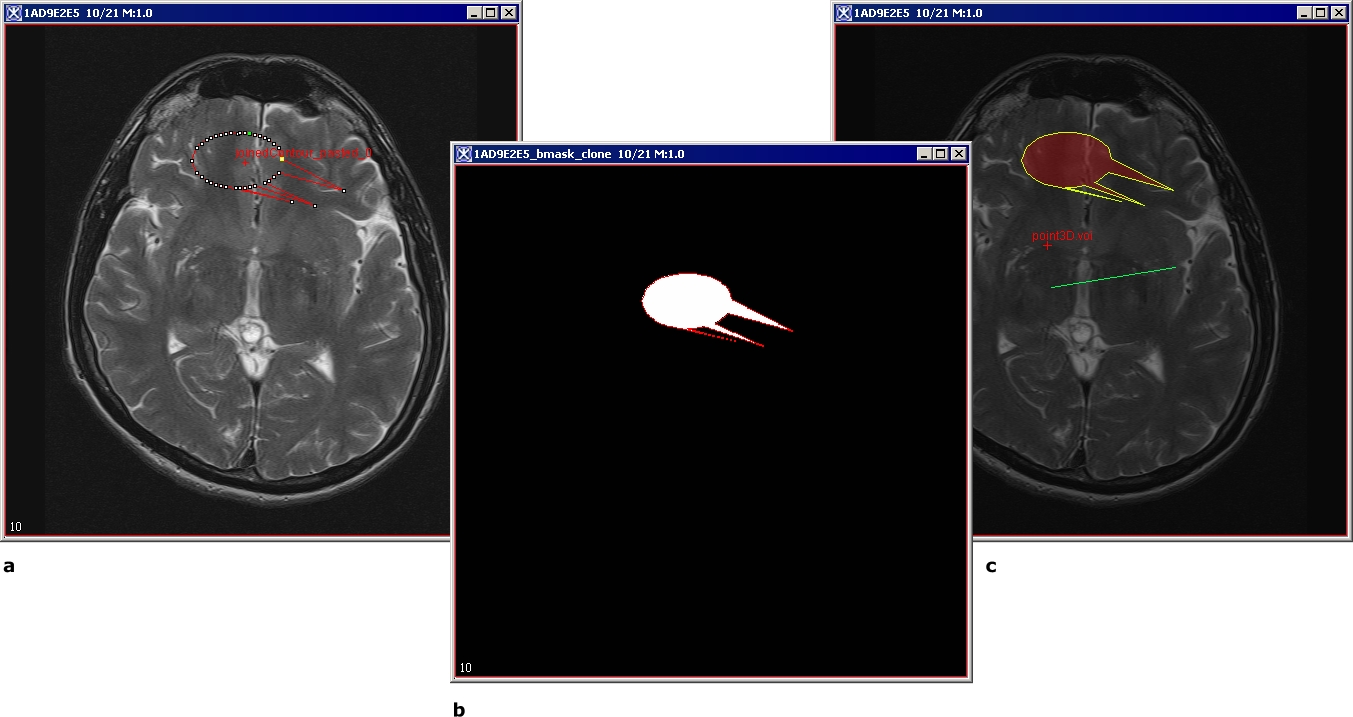

Figure 1. Converting a VOI to, a mask and then to a paint: (a) -the initial VOI, (b) - the mask created from the VOI, and (c) - the paint